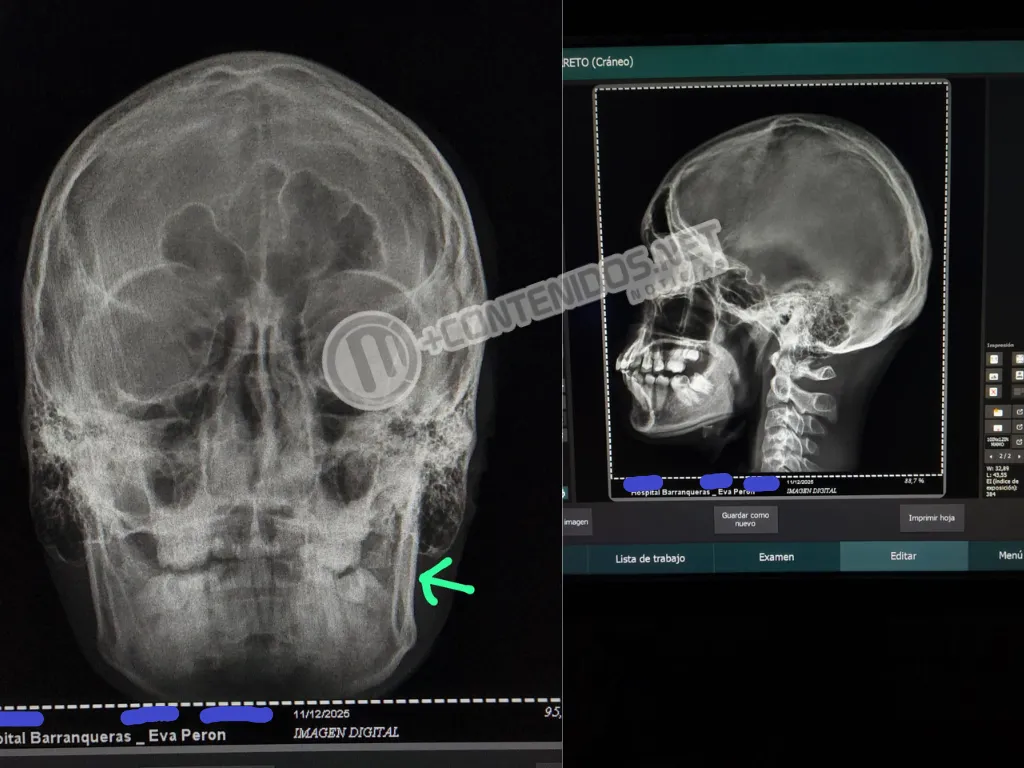

El segundo golpe le provocó una fractura mandibular, además de dejarle tres dientes flojos, múltiples golpes en la cabeza y un nuevo período de inconsciencia dentro del agua.